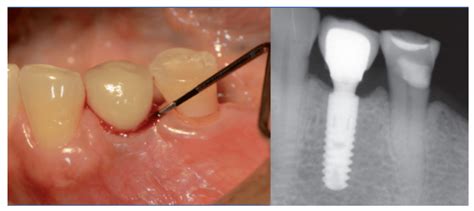

Cirugía regenerativa: en el caso de que el hueso haya sufrido daños severos, existe la posibilidad de que el odontólogo realice un estudio radiológico más avanzado para evaluar la gravedad de la pérdida de los tejidos que rodean el implante.

La cirugía bucal se completa con una implantoplastia -eliminación de espiras o roscas del implante que han quedado al descubierto por la pérdida de hueso - y pulido de la superficie del implante dental, que ayudará a dificultar en el futuro la acumulación de placa.

Para la implantoplastia aplicamos distintos protocolos de fresado con turbina dental o instrumentos de baja velocidad. En algunos casos, a la vez que fresamos, intentamos regenerar el hueso mediante biomateriales o material autólogo.